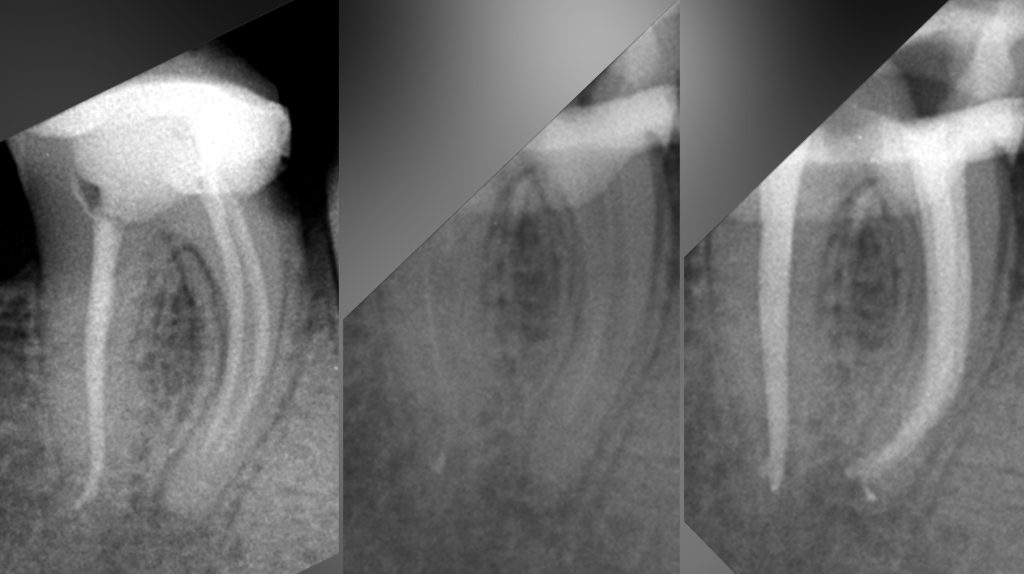

• Диагностика и лечение кариеса и его осложнений (пульпиты, периодонтиты)

• Эндодонтическое лечение корневых каналов с использованием стоматологического микроскопа